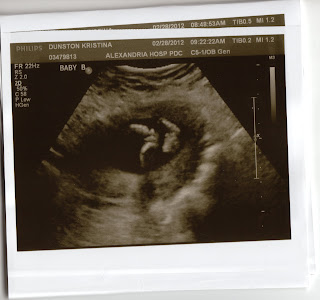

Week 19 and They Are...

Boys! Ryan will be having 2 brothers.

After a lengthy scan today, we found out that both boys are healthy with all of their digits and developing right on track. Baby A currently weighs 10 ounces and Baby B weighs 11 ounces. Mommy will now go back every few weeks to check their growth.